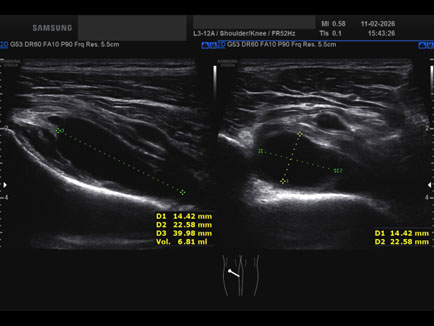

Ecografia del: 11/02/2026

Strumento: Samsung

Sonda: Lineare

Commento all'esame: rottura giunzionale muscolo-tendinea del popliteo.

Conclusioni: rottura miotendinea del muscolo popliteo sinistro (myotendinous tear of the left popliteus muscle).

Realizzazione: Dr. F. Pietro Tarini - Gubbio (PG)